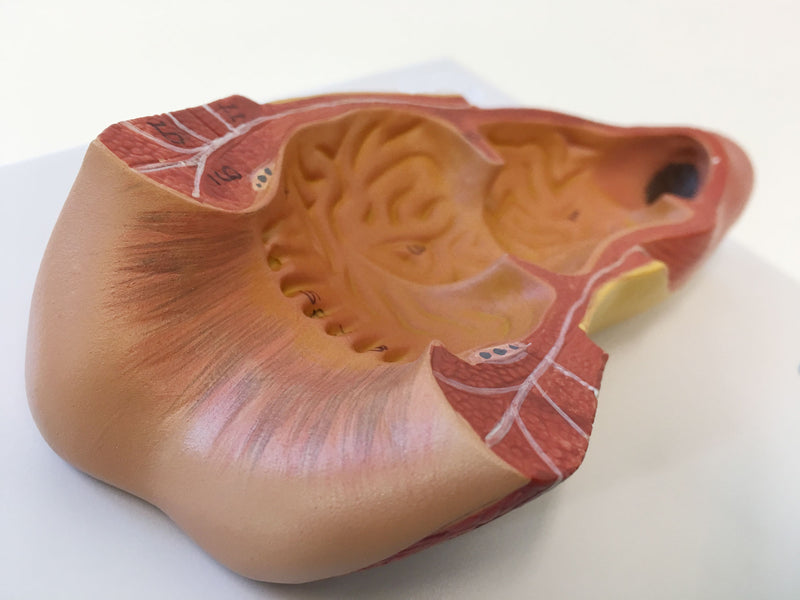

Rectum Cross-Section Model, 3X Enlarged

This model, three times life size, shows a frontal section of the human anus. The structures of the rectum, including the internal and external sphincter muscles, mucous membrane, ampullae, and anal valves are readily visible. Important anatomical structures are numbered; Accompanying an interactive 3D anatomical model with augmented reality is a great tool to encourage learning and support. This platform allows students to engage in comparative analysis of anatomical models as they compare and contrast the structure of individual organs. This initiative also provides a platform for continuing education, providing opportunities for all students to increase their knowledge of anatomy, physiology and pathophysiology.

Rectum Cross-Section Model, 3X Enlarged

This model, three times life size, shows a frontal section of the human anus. The structures of the rectum, including the internal and external sphincter muscles, mucous membrane, ampullae, and anal valves are readily visible. Important anatomical structures are numbered; Accompanying an interactive 3D anatomical model with augmented reality is a great tool to encourage learning and support. This platform allows students to engage in comparative analysis of anatomical models as they compare and contrast the structure of individual organs. This initiative also provides a platform for continuing education, providing opportunities for all students to increase their knowledge of anatomy, physiology and pathophysiology.